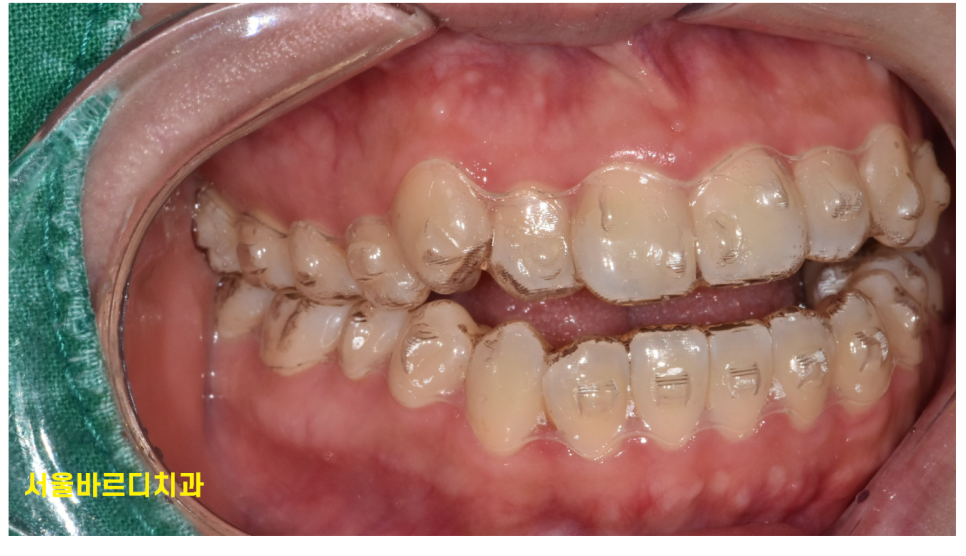

교정의 원리는 치아 뿌리를 움직여 치아를 이동시키는 것입니다.

치아에 붙은 교정 장치는 내 의지대로 제거할 수 없지만

투명 교정장치는 밥을 먹거나 하면서 제거가 가능합니다.

바로 이 부분 때문에 투명교정 실패를 경험하실 수 있습니다.

강제로 붙이고 있어야하기에 교정 효과는 확실합니다!